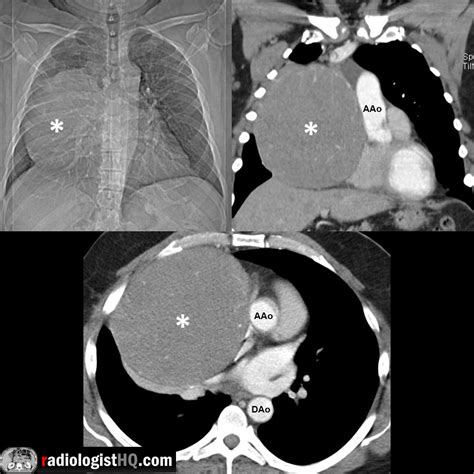

When a patient presents with symptoms such as persistent cough, chest pain, or difficulty breathing, medical professionals will initiate a diagnostic journey to confirm the presence of a Mass Anterior Mediastinum. Initial physical examinations are often followed by advanced imaging techniques, which are crucial for mapping the size, shape, and relationship of the mass to vital structures.

Chest X-ray Initial screening to identify abnormal shadows or widening of the mediastinum.

CT Scan (Contrast-enhanced) The gold standard for determining the exact location and extent of the mass.

Many patients with a Mass Anterior Mediastinum may remain asymptomatic, especially if the tumor is discovered incidentally during a routine chest X-ray. However, as the mass increases in size, it can exert pressure on surrounding structures, leading to a condition known as mass effect. Common indicators include: